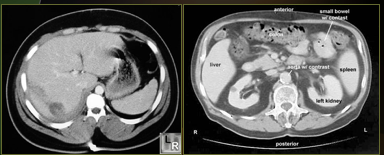

What is this image showing?

CT abdomen-liver laceration

Left image: contrast-enhanced CT of abdomen shows linear low-attenuation defect crossing the posterior aspect of the left lobe of the liver representing a laceration

Right image: Normal contrast-enhanced CT abdomen view for comparison

What is this showing?

Right image: CT pelvis without contrast demonstrating renal stone

Left image: normal contrast-enhanced CT abdomen view - for comparison